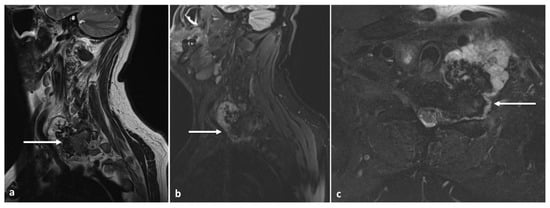

3.5. Osteochondroma

- Rajakulasingam, R.; Murphy, J.; Botchu, R.; James, S.L. Osteochondromas of the cervical spine-case series and review. J. Clin. Orthop. Trauma. 2020, 11, 905–909. [Google Scholar] [CrossRef]